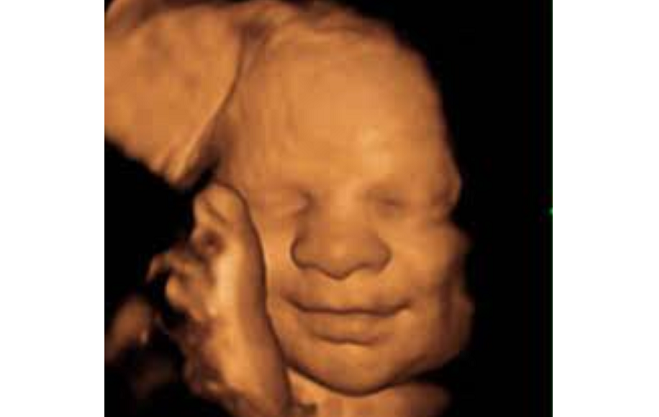

Doctors Told Mom to Abort Because Her Baby Would Die at Birth. She Refused. They Were Wrong May 22, 2026